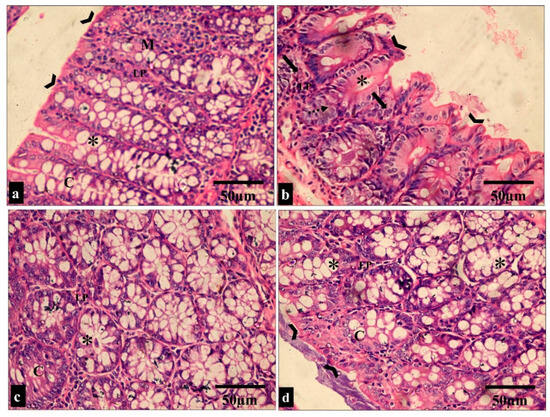

2.3.2. Histological Features